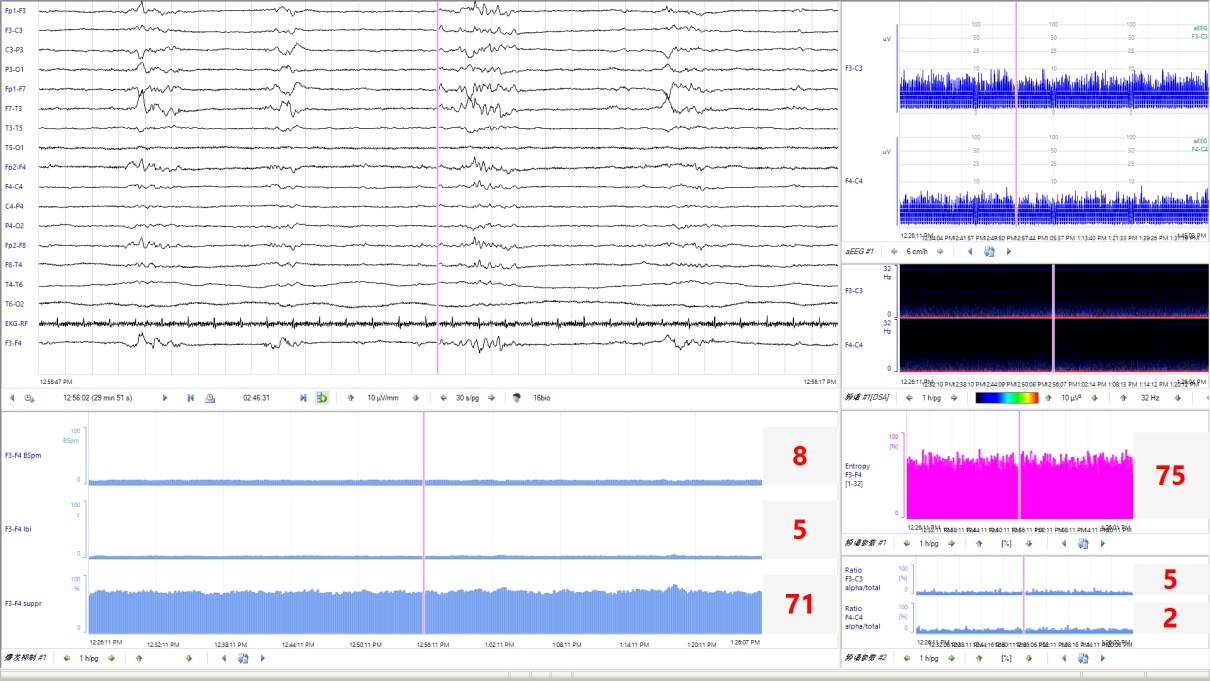

Q3:新生兒 aEEG的評價標準是什么?aEEG 主要從背景活動、睡眠周期及驚厥三方面進行評價和分類。aEEG的連續性亦被臨床廣泛關注。

睡眠周期未達到相應PMA成熟度的表現,則為睡眠周期落后于胎齡。3、驚厥發作(1) 單次發作:aEEG波譜帶短暫中斷,呈“駝峰”、“城垛”、“拱形”、“缺口”樣改變。(2) 反復發作:aEEG出現多次上述改變。(3) 驚持續狀態:既往認為發作時間超過30min或腦電圖監測過程中異常放電占總監測時間的50%以上為驚持續狀態。然而,為了減少驚厥發作時間及可能造成的神經損傷,aEEG表現為“鋸齒”樣波形時,即可根據不同的發作形式,在更短的時間窗內做出臨床治療決策。在KCNQ2基因致病性變異所致的發育及癲癇性腦病中,發作期aEEG呈現短暫上升后急劇下降(倒駝峰狀)表現,aEEG中的短暫上升圖形對應原始腦電圖的發作期圖形,急劇下降圖形對應原始腦電圖發作期后的廣泛性電壓衰減、甚至抑制圖形。4、總體評估綜上,近足月兒和足月兒可綜合aEEG的背景活動、睡眠周期及有無驚厥進行總體評估,分為正常、輕度異常和重度異常,aEEG異常提示患兒可能存在腦損傷或腦發育成熟度延遲。Q4:早產兒 aEEG的特點及其臨床意義?早產兒aEEG的背景活動、睡眠周期隨胎齡而變化。隨胎齡的增加,振幅上邊界逐漸降低,下邊界逐漸升高;睡眠周期也從最早的無法辨認到出現成熟的正弦樣變化;aEEG圖形由不連續圖形過渡為連續圖形。見表1。通過aEEG圖形變化可定性評價早產兒的腦發育情況。

Q5:aEEG診斷新生兒腦病及判斷神經發育預后的價值?aEEG可用于輔助診斷出生后6h內缺氧缺血性腦病(hypoxic-ischemic encephalopathy,HIE)的嚴重程度。窒息新生兒出生后6h內aEEG背景活動異??勺鳛殚_始亞低溫治療的準入標準,建議至少監測30min。但是不能因aEEG背景活動正常將HIE新生兒排除在亞低溫治療之外,需進一步結合臨床。建議在新生兒HIE亞低溫治療和復溫期間進行連續aEEG監測,或者每天監測一次、每次至少2h,以評價腦功能和疾病轉歸。aEEG對預測HIE新生兒預后具有一定的敏感性和特異性,應重點關注aEEG背景活動及其動態變化趨勢。行亞低溫治療的患兒,48h aEEG的背景活動和睡眠周期很關鍵,治療48h后aEEG正常的患兒預后好。復溫時無睡眠周期與預后不良相關未行/無條件行亞低溫治療的患兒,6h aEEG正常的患兒神經發育預后好;36h有睡眠周期的患兒神經發育預后好。持續的背景活動異常和缺乏睡眠周期與2歲時發育遲滯相關。代謝性腦病患兒中,70% aEEG背景活動異常,60%出現癲癇發作。Q6:如何應用aEEG篩查和準確識別新生兒驚厥?新生兒驚厥的臨床表現不典型,部分驚厥可只有電發作而無臨床表現,故可能因漏診而延誤治療,從而引起或加重腦損傷。另外,部分抗驚厥發作藥物有潛在的神經毒性。故通過持續的床旁腦電監測,可以減少漏診、避免過度診斷,并指導抗驚厥發作藥物的精準使用。aEEG對驚厥監測的優點是時效性強,可以直接、快速地在床旁開展,且可長時間監測,常用于新生兒驚厥的篩查、療效監測和評估。但由于aEEG為時間壓縮圖形,可能會漏掉振幅低、發作時間短(<30s)和起始部位距離監測電極遠的驚厥。缺乏發作期腦電圖的時空演變圖形(通常在多通道腦電圖中可以看到)是aEEG的另一個重要限制,如結合有視頻記錄的原始腦電圖,aEEG對于驚判讀的敏感度和特異度可分別達到76%和85%左右。早產兒驚厥的診斷在臨床上更為棘手,由于早產兒驚厥時臨床癥狀相對不明顯或不典型,發作期腦電活動持續時間相對短,振幅低,擴散范圍小,發作期的aEEG圖形常不易識別;新生兒重癥監護室中呼吸機的使用和各類操作干擾也可造成疑似驚厥發作圖形而誤診。因此aEEG中出現任何可疑的上下邊界短暫改變時,均需通過對比同期的原始腦電圖加以證實。視頻腦電圖(video-electrencephalography,VEEG)是新生兒驚厥診斷的金標準。沒有多導VEEG的前提下,aEEG可以用于新生兒驚厥發作的監測,但是需要同時分析原始腦電圖,最大限度避免偽差干擾導致的誤診。當臨床高度懷疑有驚厥發作而aEEG未監測到癇性放電時,建議增加導聯數量,使用8導以上帶有視頻監測的aEEG設備。有條件的醫院應進行長程vEEG監測。使用aEEG進行新生兒驚厥診斷時,建議至少有一次vEEG檢查,并與神經電生理專家密切合作。